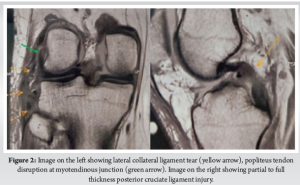

A 44-year-old surgeon presented to us with complaints of right knee pain and instability. He had an anteromedial blow to his right knee after slipping from an elevated platform while he was operating, 4 weeks back. He had no medical comorbidities and was unable to carry out his activities of daily life. On physical examination, the right knee exhibited a positive Grade 2 posterior drawer test along with a dial test showing external rotation asymmetry at 30° as well as at 90° (Fig. 1). There was Grade 3 lateral opening on varus stress and the common peroneal nerve (CPN) examination was unremarkable. Bilateral varus stress radiographs of the knee showed a side-to-side difference of more than 4 mm (Fig. 1). A bilateral lower limb scanogram showed no alignment issues, whereas the magnetic resonance imaging showed a lateral collateral ligament (LCL) tear at the fibular attachment with 1.4 cm retraction and popliteal tendon disruption at the myotendinous junction. PCL showed a partial to full-thickness tear in the midsubstance (Fig. 2). After a thorough evaluation of the physical and radiographic examination, and considering the age and active lifestyle of the patient, we decided on an Arciero-based PLC ligament reconstruction using tibialis anterior allograft. The surgery was performed according to Arciero’s “3-window technique” with a few modifications. A hockey stick incision was made, extending from the distal femoral shaft along the iliotibial band (ITB) proximally, and continuing distally between Gerdy’s tubercle and the fibular head. The third window was created first, inferior to the biceps femoris, where the CPN was identified, protected and exposed distally up to the fibula head. The second window was made between the anterior border of the biceps femoris and the posterior border of the ITB, for future passage of the graft. The first window was then developed by splitting the ITB along its midline and centered over the lateral femoral condyle (Video 1).